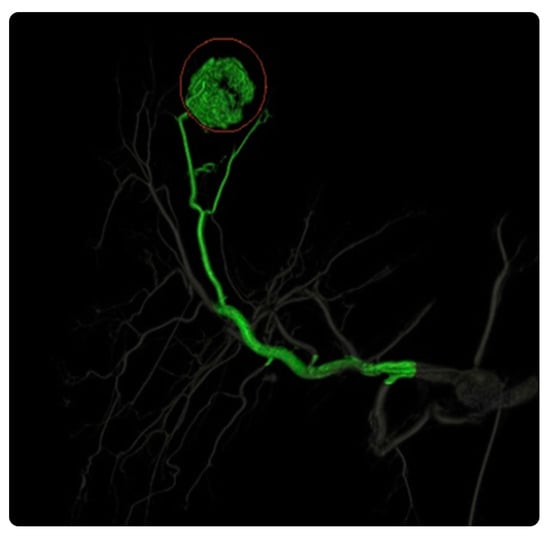

3.2.3. EmboGuide

EmboGuide with XperCT Dual provides workflow-based embolization guidance and automatically detects and treats tumors and vessel suppliers to multiple lesions. Compared with DSA, EmboGuide can detect 50% more HCC feeders [37,38]. Furthermore, it overlays 3D reconstructions on X-ray images to facilitate navigation to an embolization target and maximize the performance of TACE procedures [37,38]. Our search revealed no evidence of its practical clinical impact (Figure 7).

3.4.7. FlightPlan for Liver

This postprocessing liver embolization device can detect liver tumor-feeding vessels and vessels traveling to the tumor vicinity with 95% sensitivity. It can aid physicians in determining the hepatic arterial anatomy during embolization procedures by highlighting hypervascular hepatic lesions. Similar to data on hypervascular tumors, hepatic vasculature data can be easily extracted by clicking on the catheter tip’s location with the target tool [77] (Figure 13).

The available practical evidence is as follows.

Joo et al. [79] conducted a retrospective observational study to compare the efficiencies of FlightPlan for Liver and DSA in 50 patients with 80 HCC nodules. They concluded that FlightPlan for Liver was more practical than DSA, particularly for detecting small HCCs and small feeding arteries, which are often challenging to detect.

Iwazawa et al. [80] conducted a prospective observational study to evaluate the efficiency of FlightPlan for Liver in identifying the vessels responsible for arterial bleeding during endovascular embolization in five patients with visceral arterial hemorrhages; they found that, due to the accurate, rapid identification of damaged vessels, this software was useful for guiding endovascular embolization, even for visceral arterial hemorrhages.

Ronot et al. [81] conducted a multicenter retrospective observational study to compare the abilities of arterial cone-beam CT and FlightPlan of identifying tumor-feeding arteries in 45 patients with 66 hypervascular HCCs who underwent conventional chemoembolization. They concluded that using the software ensured precise and fast identification of the tumor-feeding vessels.

Durack et al. [78] conducted a unicentral retrospective observational study to compare arterial CBCT using FlightPlan and conventional DSA during TACE in 34 consecutive patients with unresectable hypervascular primary or secondary liver tumors who underwent selective bland or drug-eluting bead TACE. The software was found to have a higher sensitivity for detecting tumor feeder vessels with a reasonable radiation dose and procedural time.